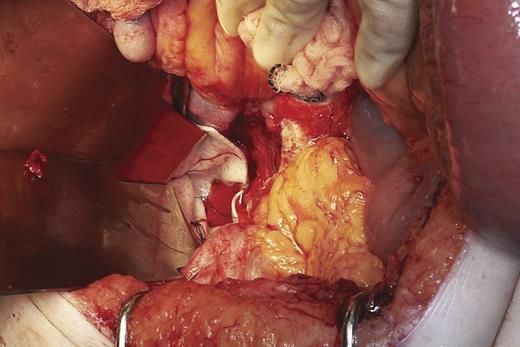

At operation, small bowel obstruction was found with volvulus of a loop of ileum around an adhesion at the neck of the perineal hernia (Fig. 2). Around 80 cm of gangrenous mid-ileum was resected and a primary end-to-end anastamosis performed. After thorough washout of the abdomen and pelvis, the wide pelvic floor defect was bridged with Strattice™ Tissue Matrix, secured in place with 2.0 prolene sutures (Fig. 3). An omental pedicle graft was used to cover the mesh and fill the pelvis. One abdominal tube drain and two perineal suction drains were inserted and removed over the course of the next 7 days.

Laparotomy findings of transition point of small bowel obstruction at neck of perineal hernia.